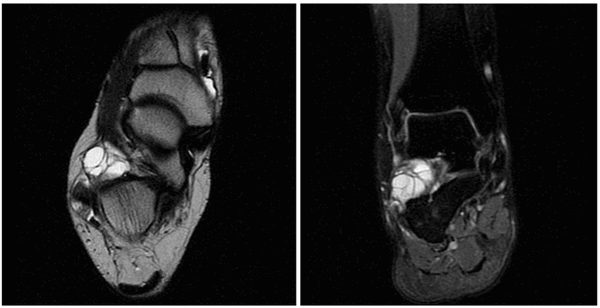

Как выглядит ганглиевая киста на МРТ? Это одно- или многокамерное кистозное образование с равномерно гипоинтенсивным сигналом на Т1 ВИ, гиперинтенсивным сигналом на Т2 ВИ и STIR, накапливающее контраст на основе гадолиния в виде «ободка». В некоторых случаях обнаруживается также повреждение сухожилия вблизи кисты.

На УЗИ ганглий выглядит как одно- или многокамерное образование с тонким «ободком» и множественными перегородками, чаще всего анэхогенное, реже с эхогенными включениями. Может обнаруживаться также акустическое усиление. Для поиска кровотока в образовании и признаков, позволяющих отличить ганглий от опухоли, используется цветовая или энергетическая допплерография. Ультрасонография, допплерография, МРТ — наилучшие методы визуализации сухожильного ганглия.